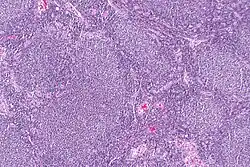

Micrograph of a follicular lymphoma, showing the characteristically abnormal lymphoid follicles that gave the condition its name. H&E stain. | |

Follicular lymphoma (FL) is a cancer that involves certain types of white blood cells known as lymphocytes. This cancer is a form of Non-Hodgkin Lymphoma and it originates from the uncontrolled division of specific types of B-cells (centrocytes and centroblasts). These cells normally occupy the follicles (nodular swirls of various types of lymphocytes) in the germinal centers of lymphoid tissues such as lymph nodes. The cancerous cells in FL typically form follicular or follicle-like structures (see adjacent Figure) in the tissues they invade. These structures are usually the dominant histological feature of this cancer.[1]

The diagnosis of FL depends on examining involved tissues for histological, immunological, and chromosomal abnormalities that are indicative of the disease. FL usually involves enlarged lymph nodes populated by abnormal follicles (see adjacent picture) that when examined histologically contain a mixture of centrocytes or centroblast surrounded by non-malignant cells, mostly T-cells. The centrocytes, which typically outnumber centroblasts, are small to medium-sized B-cell lymphocytes that characteristically exhibit cleaved nuclei; the centropblasts are larger B-cell lymphocytes without cleaved nuclei.[9] Rare cases of FL may show lesions that contain tissue infiltrations dominated by B-cells with features of precursor (i.e. "blast") cells, monocytes, or malignant mantle cells such as those found in mantle cell lymphoma.[1] Immunochemical analyses reveal that these cells generally express B-cell surface markers including the CD10 (60% of cases), CD20, CD19, CD22, and CD79 but not CD5, CD11c, or CD23 cell surface proteins;[2] genomic analyses reveal that these cells contain t(14:18)(q32:q21.3) translocation (85–90% of cases), 1p36 deletions (60–70% of cases), and with far less frequency the other genomic abnormalities listed in the above sections on Pathophysiology and Presentation and course. None of these protein markers or genomic abnormalities are diagnostic for FL, e.g. the t(14:18)(q32:q21.3) translocation is found in 30% of diffuse large B-cell lymphoma and in a small number of reactive benign lymph nodes. Rather, the diagnosis is made by a combination of histological, immunological, and genomic abnormalities.[2] According to World Health Organization (WHO) criteria, follicular lymphoma can be classified morphologically by the relative amount of centroblasts. However, such classification is optional, due to poor reproducibility and little difference in prognosis and treatment, except that a lymphoma with almost only centroblasts may be diagnosed as a diffuse large B-cell lymphoma (DLBCL).[48] The optional classification of follicular lymphoma is as follows:[49]